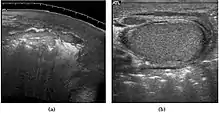

The incidence of infertility is decreased if surgical orchiopexy is carried out before the 1–3 years but the risk of malignancy does not change. Because of the superficial location of the inguinal canal in children, sonography of undescended testes should be performed with a high frequency transducer. At ultrasound, the undescended testis usually appears small, less echogenic than the contralateral normal testis and usually located in the inguinal region [Fig. 29]. With color Doppler, the vascularity of the undescended testis is poor.

![Fig. 29. Undescended testis. (a) Normal testis in the scrotum. (b) Atrophic and decreased echogenicity of the contralateral testis of the same patient seen in the inguinal region.[citation needed]](../I/Scrotal_ultrasonography_of_undescended_testis.jpg.webp) Fig. 29. Undescended testis. (a) Normal testis in the scrotum. (b) Atrophic and decreased echogenicity of the contralateral testis of the same patient seen in the inguinal region. Fig. 29. Undescended testis. (a) Normal testis in the scrotum. (b) Atrophic and decreased echogenicity of the contralateral testis of the same patient seen in the inguinal region.